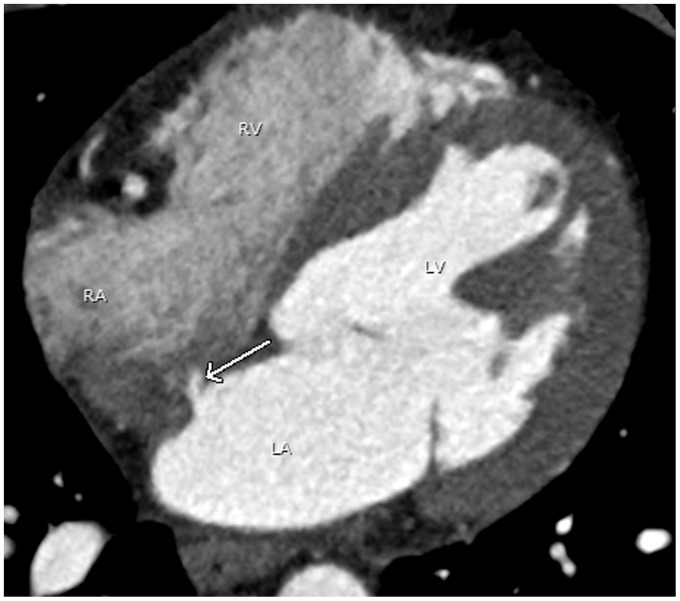

Advances in computed tomography have led to continuous improvement in cardiac imaging. Dedicated postprocessing capabilities, faster scan times, and cardiac gating methods reveal details of normal cardiac anatomy and anatomic variants that can mimic pathologic conditions. This article will review normal cardiac anatomy and variants that can mimic disease. Radiologists should be familiar with normal cardiac anatomy and anatomic variants to avoid misinterpretation of normal findings for pathologic processes.